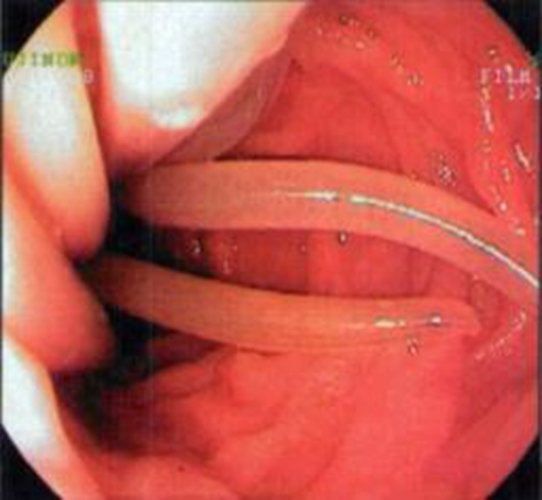

蛔蟲病蛔蟲外形

A:腸絛蟲病以大便常規檢測,見到有排出的絛蟲節片為主要診斷依據。常見的有豬帶絛蟲病和牛帶絛蟲病,主要是因為進食了含有囊蚴的豬肉或者牛肉而出現感染。治療方面主要是驅蟲治療,比如說用吡喹酮。一般情況不需要導瀉療效都可以達到95%以上。另外可以口服甲……

A:絛蟲病是因為各種成蟲寄生在人體的小腸而引起的疾病的總稱。比較常見的有豬帶絛蟲病和牛帶絛蟲病。主要是因為進食了含有囊蚴的豬肉或者牛肉而出現感染。它的潛伏期比較長,一般要需要幾周的時間。患者通常沒有什麼明顯的不適,一般是在大便中發現白色帶狀節片……